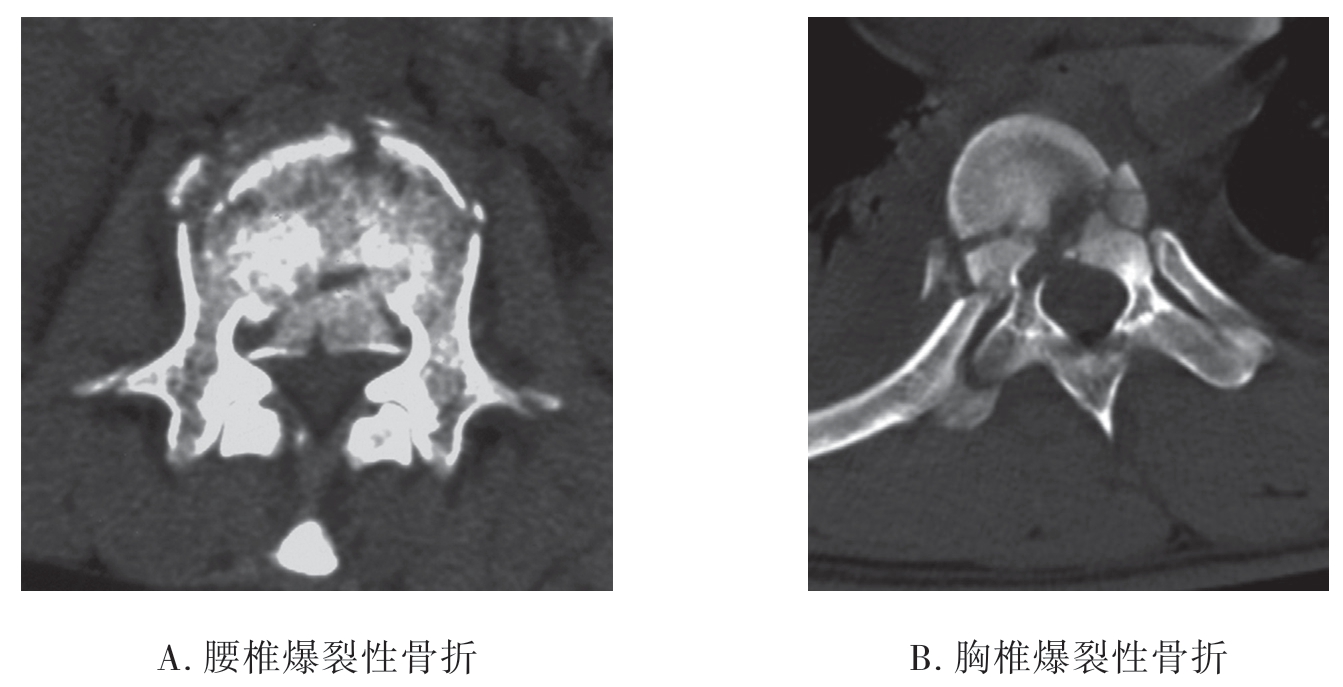

胸腰椎爆裂性骨折主要是受到垂直方向暴力或垂直方向合并屈曲压缩暴力导致椎体破裂,并向四周膨出、移位。

1.X线平片 脊椎受到垂直方向暴力的作用椎体可发生粉碎性骨折。椎体压缩变扁,椎体及附件的骨折片向前后左右各方向移位。X线对爆裂性骨折的显示不如CT检查(图7-2-14)。

2.CT检查 脊椎骨结构复杂,互相重叠,CT应用图像后处理技术,可清晰地显示脊椎骨折类型、骨折片移位程度、附件骨折、小关节脱位、椎管变形及狭窄等变化。而CT检查的重点是观察脊髓有无受压情况。

(1)脊椎骨折:显示椎体、椎板、上下关节骨折及其移位,严重者椎管内可见骨碎片,椎管狭窄。

(2)椎管内血肿:①硬膜外血肿,血肿呈半圆形高密度影,硬膜囊变形较局限;②硬膜下血肿,血肿呈半圆形高密度影,形态不规则,边界不清楚;③脊髓内血肿,脊髓内高密度影,形态不规则,边界不清楚。

(3)创伤性椎间盘脱出:显示椎间盘局限性突入椎管使硬膜囊变形、脊髓移位(图7-2-15)。

图7-2-15 CT示爆裂性骨折